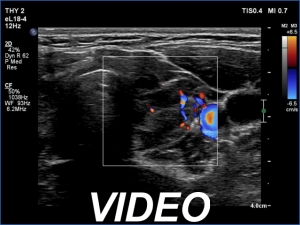

Ultrasonography. The thyroid was echonormal and had hypoechoic areas. The echogenicity index exceeded 50%. The pattern did not correspond to nodule. The vascularity was not specific.

Comment. This is the most common presentation of Hashimoto's thyroiditis, unfortunately not infrequently misinterpreted as a multinodular goiter. The multiplicity and the irregular borders of the discrete lesions are the main clues to avoid misinterpretation of these lesions as nodules.